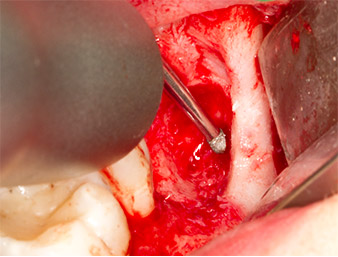

After block and local anaesthesia, the operating site was opened up and the soft tissue exposed for buccal retromolar access (Fig. 3).

The tissue above the root remnant was not completely ossified and consisted for the most part of granulation tissue modified by inflammation (Fig.4).